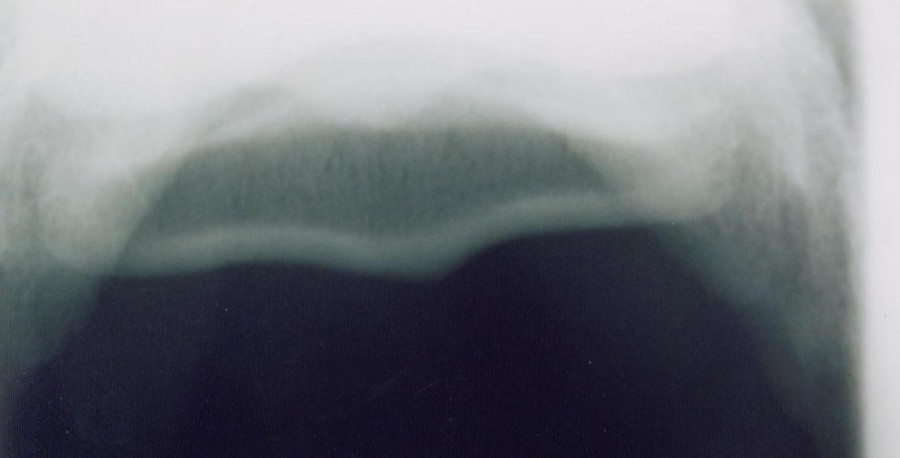

Lundi radios, et mardi, hier, il passe pour me montrer que... les radios sont saines, rien d'apparent, il soutient qu'il pourrait devenir naviculaire et me suggère un traitement au tildren en prévention, mais qui coûte apparemment tres cher....